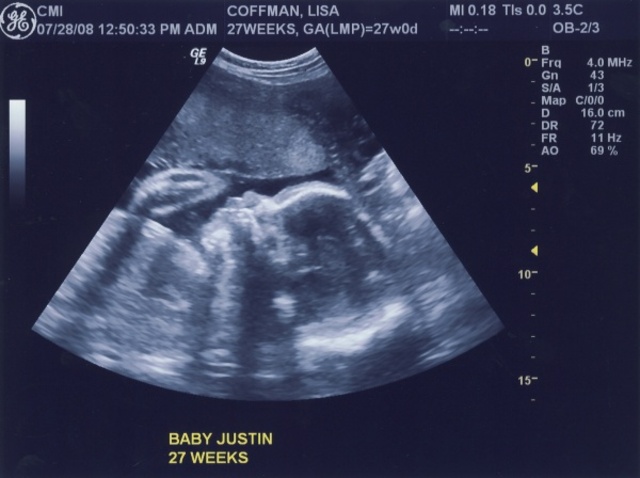

• Fully Functioning (28 Weeks)

Fully Functioning (28 Weeks)

The baby's lungs have developed enough that if she were born, she would be able to survive on her own.